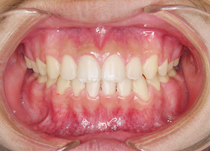

CASE2:成人(永久歯が生えそろった方)の症例

<治療前>前歯から犬歯まで隙間があります

<治療後>上下の隙間が改善されました

治療後

CASE2:成人(永久歯が生えそろった方)の症例治療後